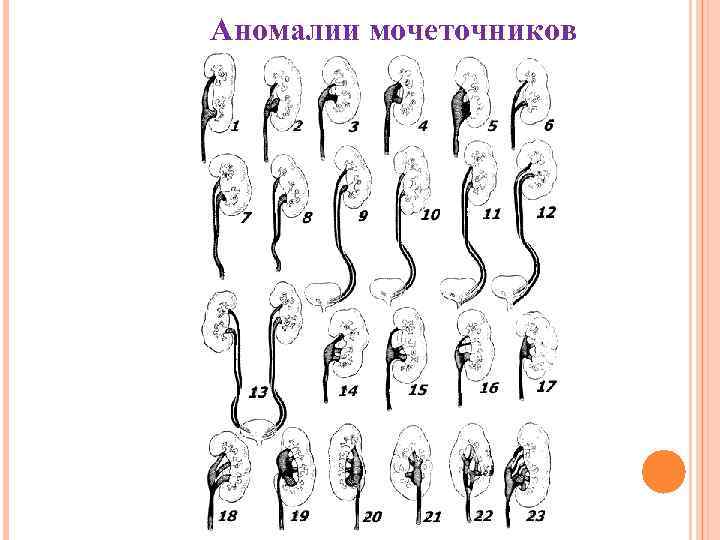

Аномалии мочеточников

Аномалии мочеточников